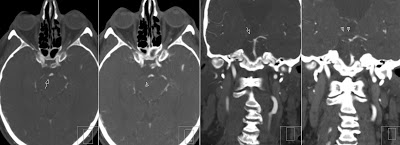

First image shows Acute Lacunar Thalamic Infarct on the right side with corresponding second image showing prior study 11 hours before, that also depicts acute infarction.

CTA shows occlusion of the P1 segment of the right Posterior Cerebral Artery (arrows). You can also (with some difficulty) depict a thromb in this segment (arrowheads).